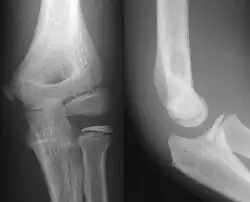

- Elbow - AP and Lateral. Radial head projections available on request

-

Lateral projection -

Anteroposterior projection -

Left elbow by 30 degrees internal oblique projection -

Left elbow by 30 degrees external oblique projection

- Knee - AP and Lateral. Intra Condular projections on request

Right knee, anteroposterior -

Right knee, lateral -

Patella, (slightly skew) skyline